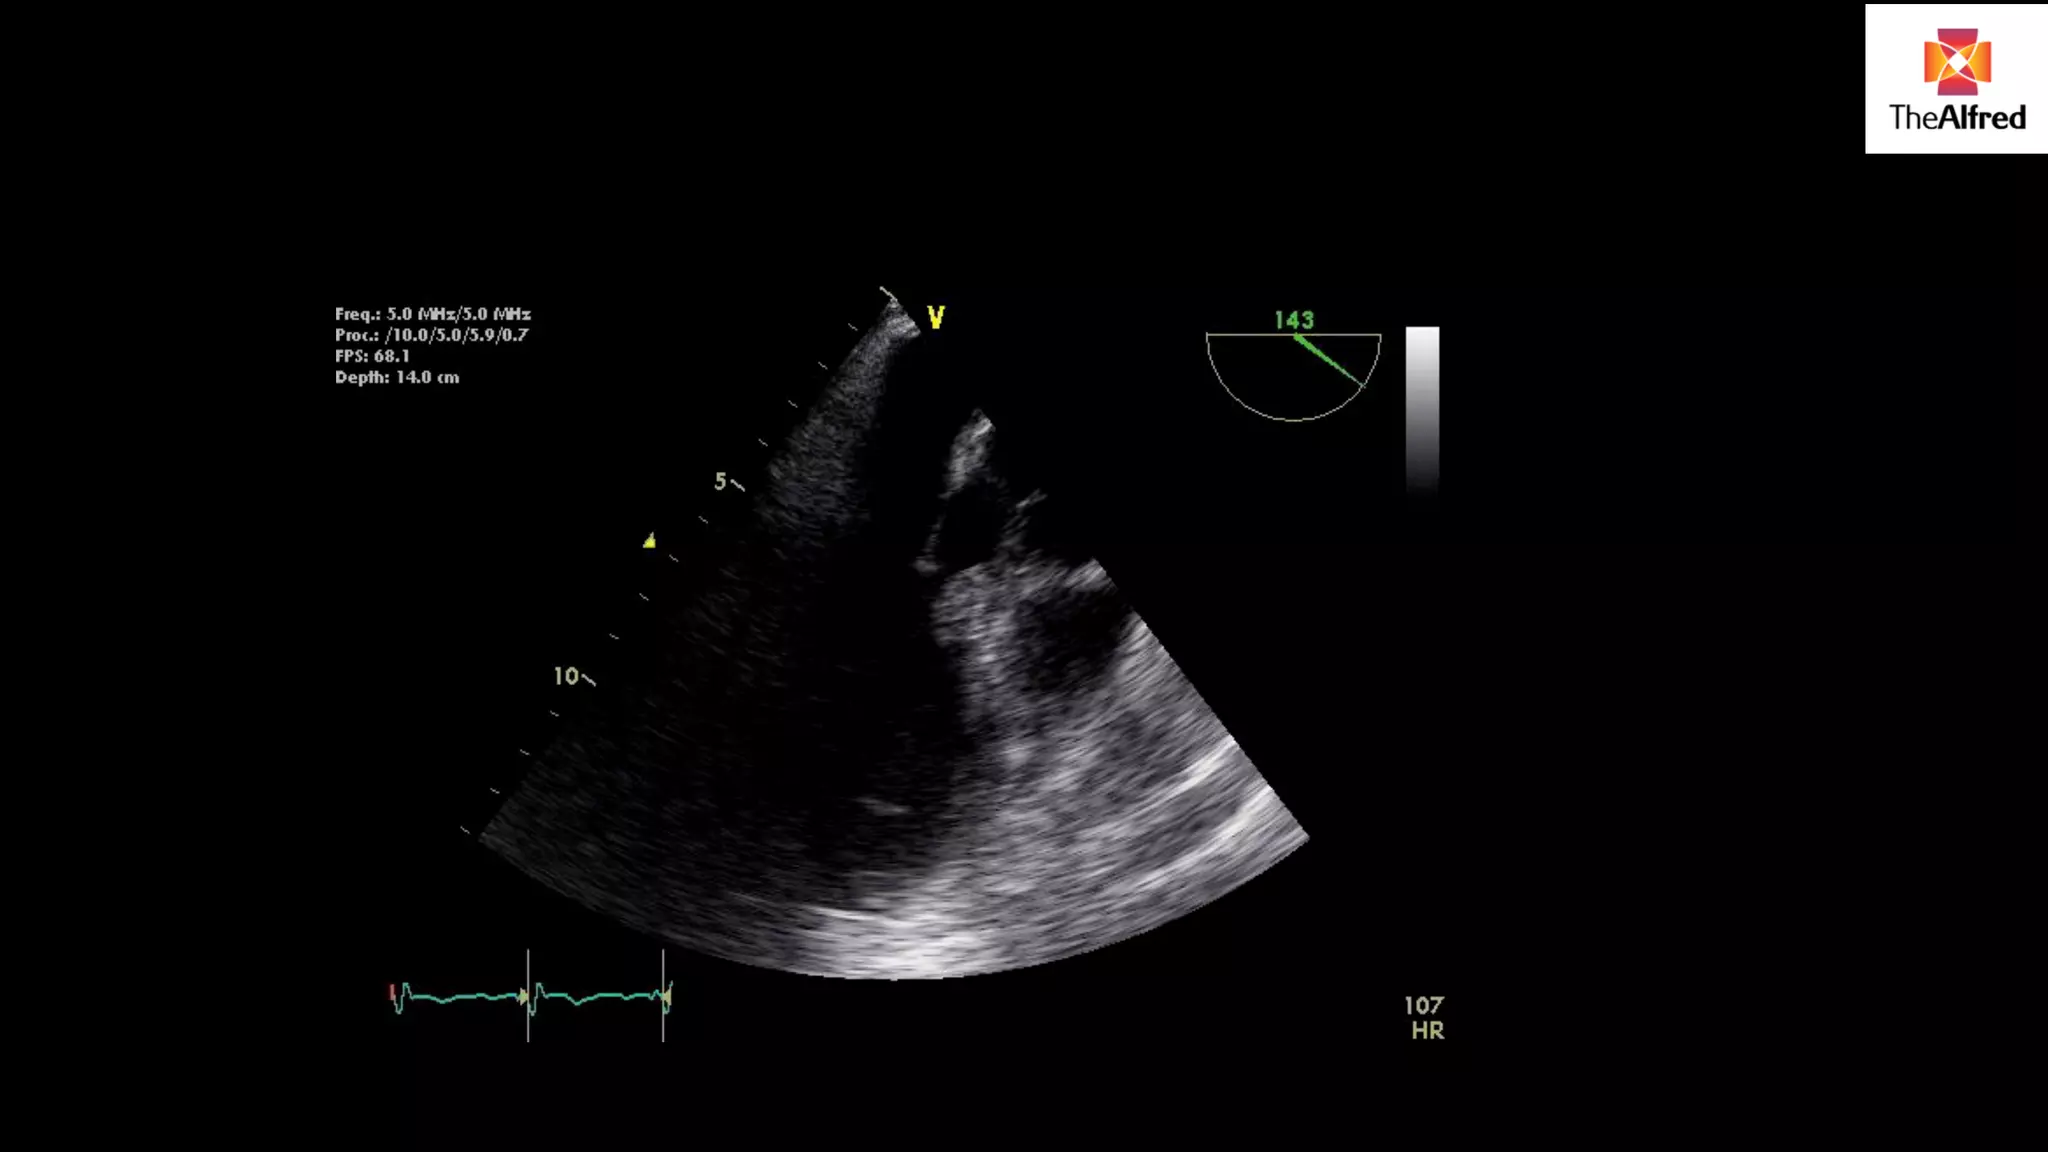

CASE STUDY 72yo man post CAGs X 2 and AVR “Good” LV intra-operative Hypotensive MAP 65 PAC: CO 3.6/ C.I 1.8 PA pressures 56/30 CVP 18 Management? Inotropes and vasopressor: Milrinone 10 mcg/min, adrenaline 7 mcg/min, Noradenaline 17 mcg/min

DIFFERENTIAL ? Tamponade ? Graft ischaemia

Dx LV outflowtract obstruction (with SAM) Rx: Avoid hypovolaemia Avoid inotropy Maintain afterload

DYNAMIC LVOTO Seenafter cardiac surgery classically AVR Seen in non-cardiac surgery patients also esp elderly females with hx HTN and DM Haemodynamic situation worsened by inotropes and can contribute to downward spiral